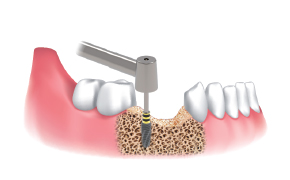

Secuencia de obtención :

Sitio de implante utilizando Ø3.5/4.0

Fresa de recolección con escudo de silicona.

Fresa punta para marcar sitio de obtención y de implante.

Seleccionar fresa Ø3.5/4.0 e insertar el stopper en la fresa seleccionada. Luego poner la pantalla en el stopper Ø3.5&4.0.

Fresar entre 300 a 500 RPM con irrigación y obtener las limallas de hueso.

Desensamblar el escudo de silicona, el stopper y colectar las limallas de hueso para la regeneración ósea.

Utilizar fresa final (igual o mayor a Ø3.5/4.0) de acuerdo al protocolo de fresado del fabricante y al plan de tratamiento.

Instalar implante.

Aplicar las limallas de hueso obtenidas en el sitio de regenaración.